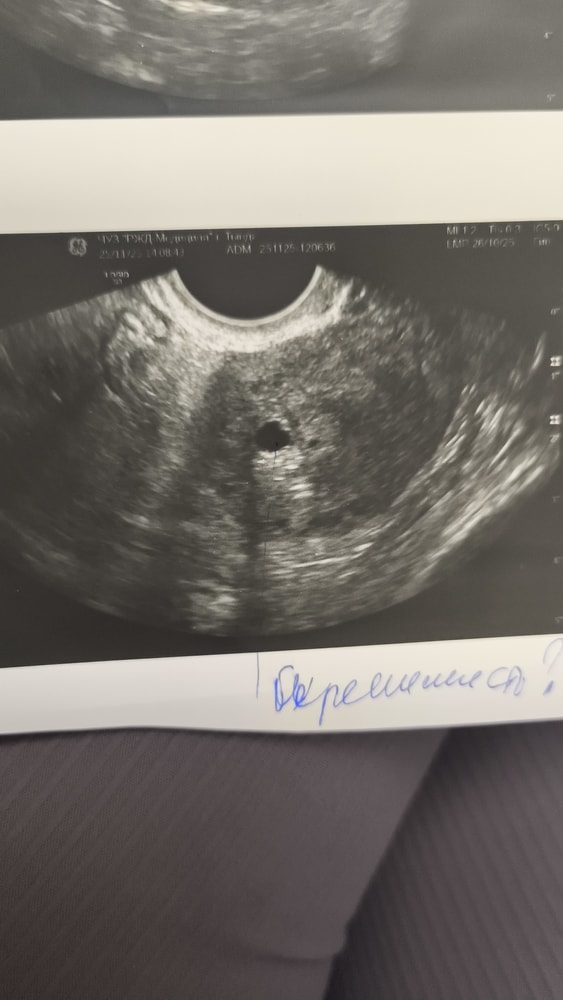

Сегодня 2 дз, тесты яркие. Хгч сдать нет возможности. По месячным 4 н 2 дня. Сегодня началась мазня, не алая, но коричнево-красная. На узи экстренно пя в матке, свд 4,5 мм желточного мешочка нет, наверное рано и не должно. Подключили Транексам , Утрожестан, Прогинову, так как забеременела на маленьком эндометрии и сейчас всего 7.5 мм. У кого был хороший исход. Плачу, сил нет

Диана , конечно. У меня при 6 мм не было ещё, и срок 4н5д, не было ничего, только яичко)

У вас хорошее яичко,кругленькое) растите)